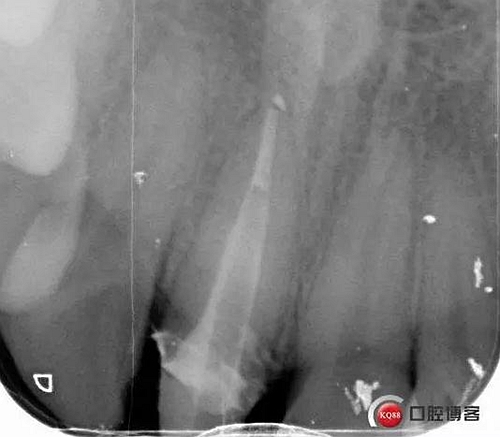

術(shù)后牙片可以看出樁的長度有明顯增加。到達(dá)預(yù)備長度。術(shù)后齦緣高度與鄰牙一致